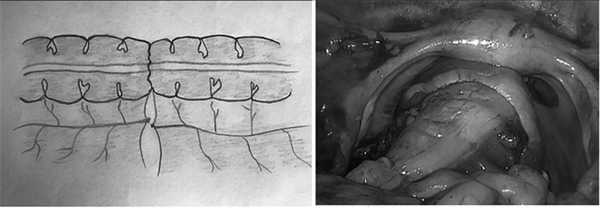

После лапароскопической мобилизации левой половины толстой кишки с опухолевым образованием проводят подготовку кишки для формирования толстокишечного анастомоза. С этой целью проксимальнее опухолевого образования кишечную стенку обрабатывают для пересечения, удаляют брыжейку и жировые подвески на расстоянии 1,5 см в продольном направлении. Затем накладывают две поперечные лигатуры на толстую кишку, используя интракорпоральный самозатягивающийся узел (рис. 1). В качестве лигатур желательно применять плетеный синтетический рассасывающийся шовный материал с полимерным покрытием с добавлением стеарата кальция, который формирует надежный узел. Толстую кишку рассекают между лигатурами аппаратом Ligasure (Covidien, США), что обеспечивает герметизацию полости кишки и предотвращает бактериальную контаминацию брюшной полости (рис. 2). Выполняют минилапаротомию по Пфанненштилю. Извлекают удаленную толстую кишку с опухолевым образованием. Экстракорпорально выполняют резекцию толстой кишки с опухолью. Фиксируют головку циркулярного сшивающего аппарата CDH-29 (Ethicon Endo-Surgery, США), используя кисетный шов, в просвете толстой кишки. Проксимальный отдел толстой кишки совместно с головкой сшивающего аппарата, фиксированной кисетным швом, погружают в брюшную полость. Минилапаротомный разрез ушивают. Накладывают карбоксиперитонеум. Трансанально вводят сшивающий аппарат. Прохождение интегрированного выдвигающегося троакара через самозатягивающийся узел дистального отдела резецированной толстой кишки, собранной в кисет, является одним из принципиальных моментов наложения лапароскопического интракорпорального термино-терминального циркулярно-перитонизированного толстокишечного анастомоза (рис. 3). Тракцией и антитракцией штоком циркулярного сшивающего аппарата CDH-29 (Ethicon Endo-Surgery, США) обеспечивают равномерное распределение стенки кишки вокруг интегрированного троакара по типу «шатра» (рис. 4). Далее формируют двухрядный аппаратный скрепочный шов. После закрытия скрепок острым ножом обрезают излишки тканей внутри шва, происходит атравматическое формирование интракорпорального циркулярно-перитонезированного термино-терминального анастомоза (рис. 5).

Рис. 1. Наложение двух параллельных лигатур на стенку кишки, используя интракорпоральный самозатягивающийся узел, проксимальнее опухолевого процесса.

Fig. 1. The application of two parallel ligatures on the wall of intestine, using intracorporeal self-tightening node, proximal to the pathological tumor process.

Рис. 2. Пересечение толстой кишки между лигатурами.

Fig. 2. Intersection of the colon between the ligatures.